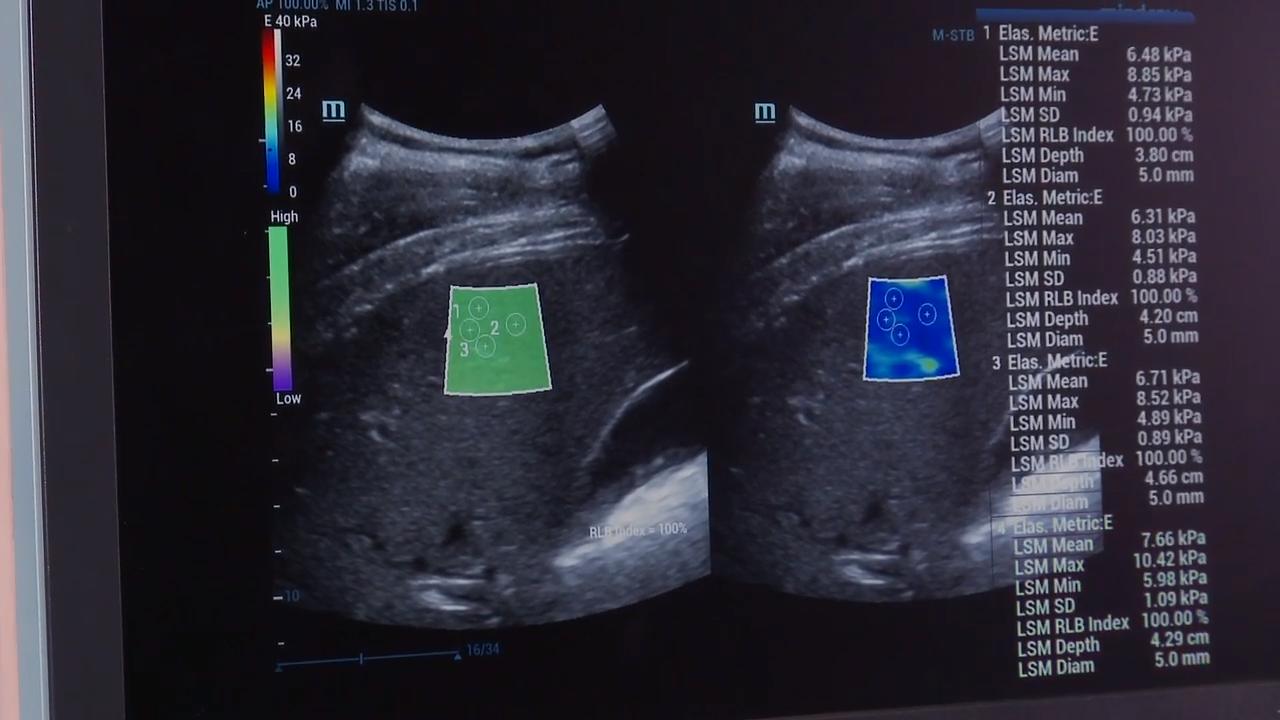

Endelmonobgyn